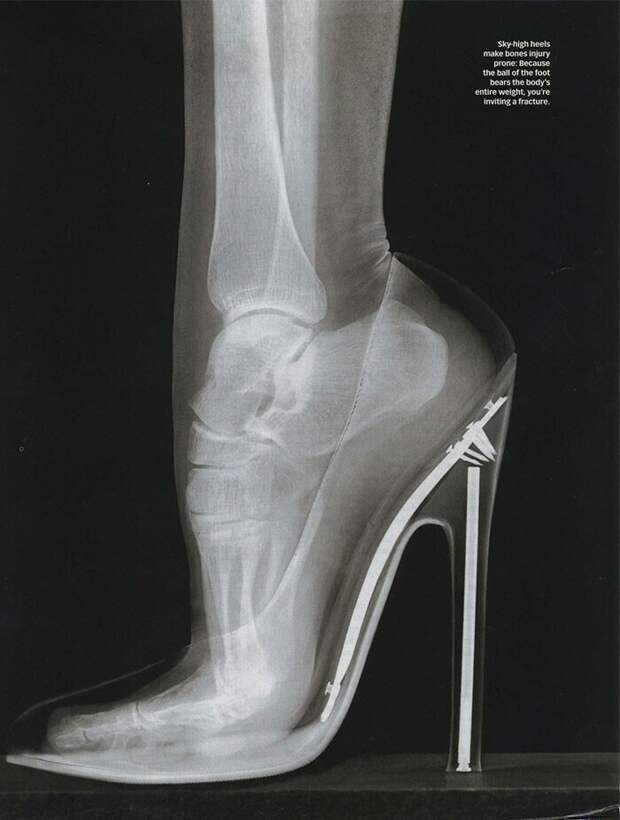

Рентген женской стопы на шпильке